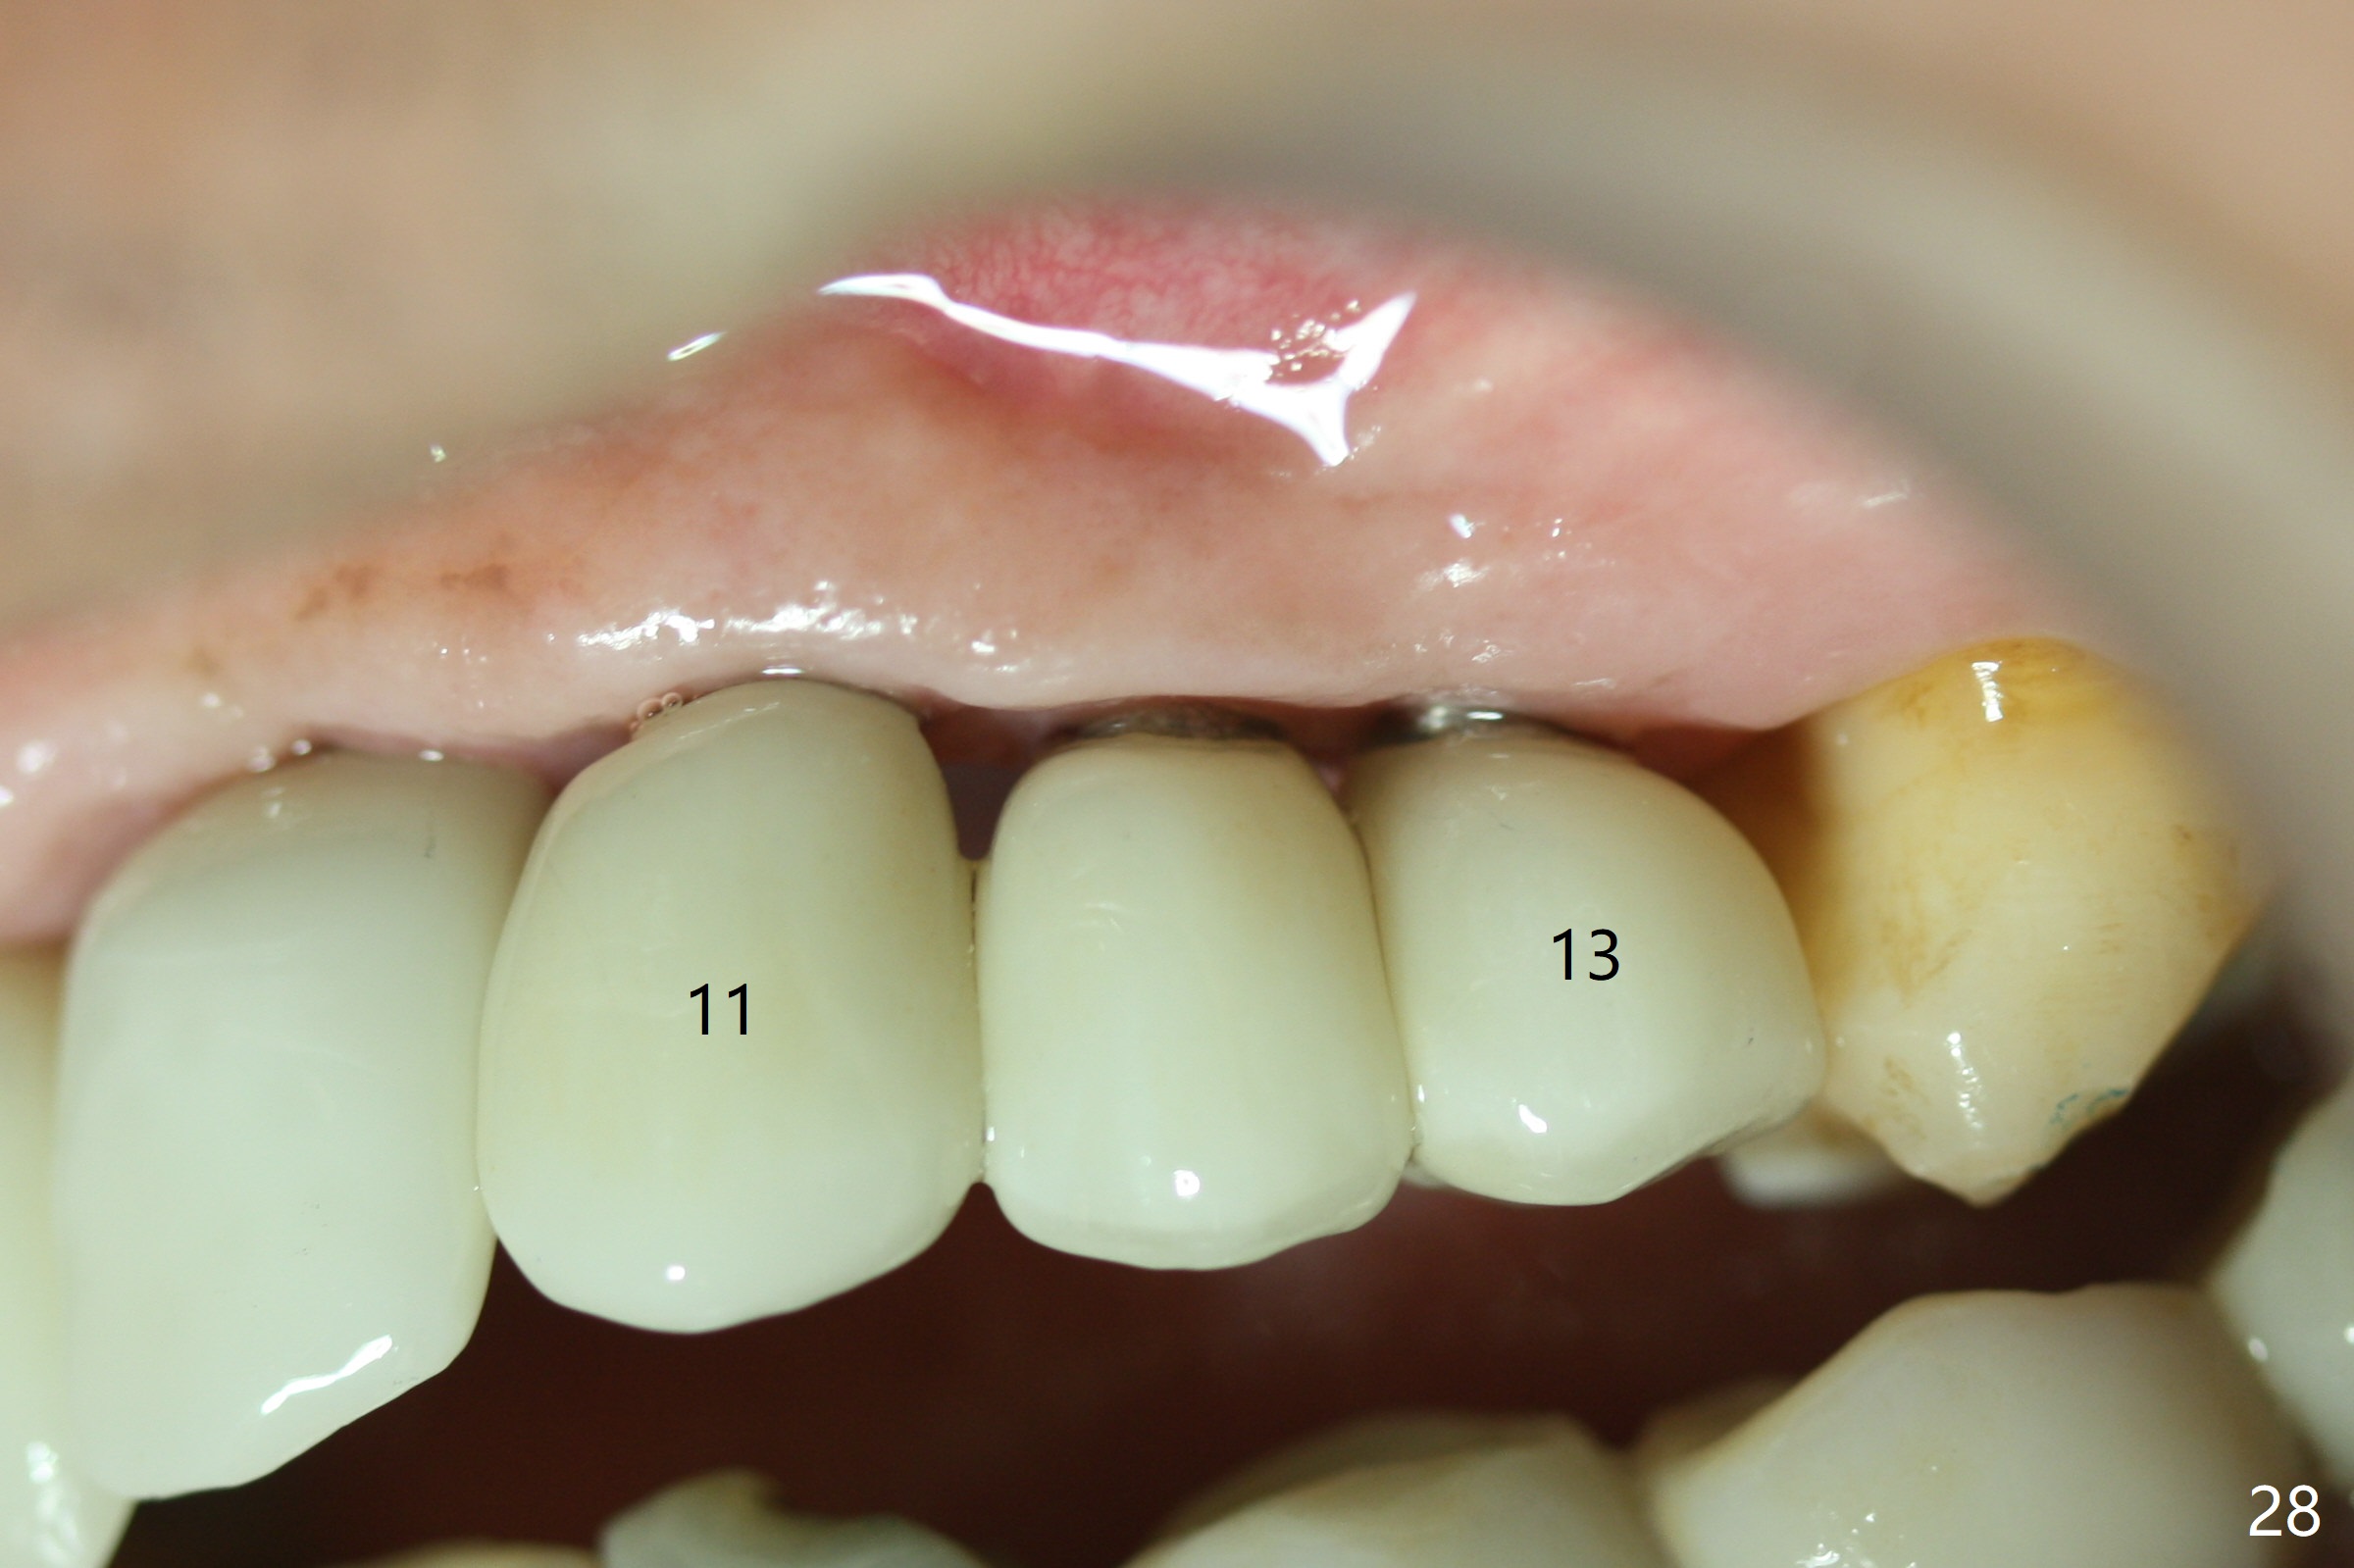

The gingiva remains healthy with use of water pik at #8-10 (4 months post cementation) and at #11-13 (immediately post cementation (1 year 2 months postop, Fig.27,28), while bone loss is minimal (Fig.29-31). The patient is pleased with convenience of the fixed restoration.